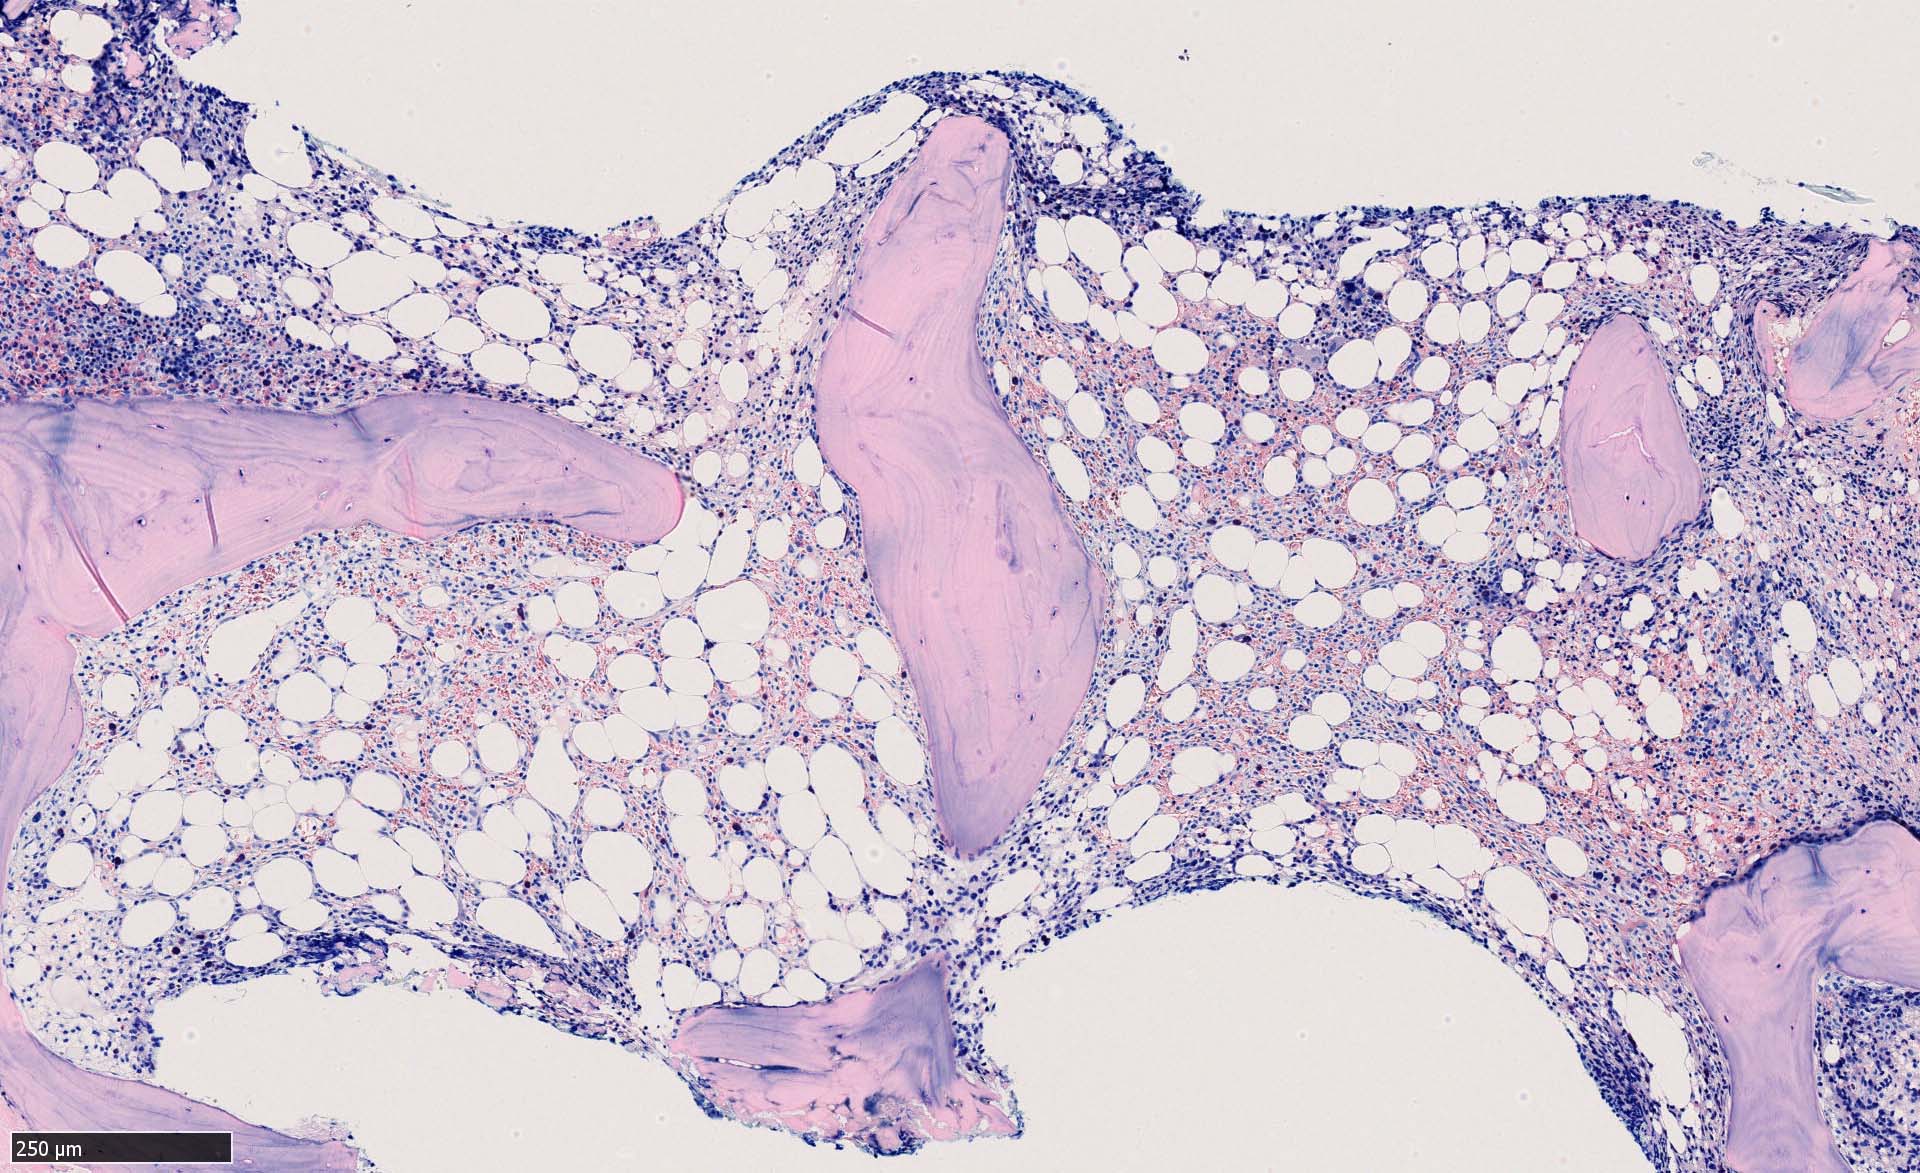

骨髄生検

bone marrow trephine biopsy: dry tapのため骨髄生検が行われる. cellularityは40-80%とhypercellular marrow. 流れのある細胞配列は線維化を疑わせる.

ASD-G 低倍率所見では赤芽球血島は幼若赤芽球の集簇巣が散在する, 顆粒球系細胞(ASDに赤く染色される)は減少,granulopoietic hypoplasiaを呈する.疎な集簇を示すmast cellsの増加がある.

ASD-G陰性の細胞がびまん性に増加しているように見える.

ASD-Giemsa陰性の細胞がシート状に増殖する. 核はクロマチン濃染, 核小体は不明瞭.類円形, 卵円形, くびれを持つ多稜形核, 長円形いびつで屈曲した核, など多彩. 細胞質は淡清色調, 広く淡明. 赤芽球血島は幼若赤芽球のみで形成される異形成像を示す. やや離れて成熟赤芽球が疎な集簇を示す.

Ag染色では, 疎な弾性線維が増生し,増殖細胞を小胞巣状に分画するいわゆる「lymphomatoid pattern」を呈する. 本例では, Mgkに異形成所見がある.